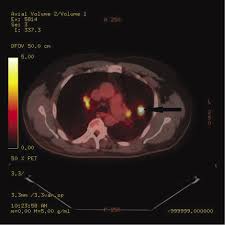

Can Lung Cancer Be Mistaken For Sarcoidosis - Case Report Pulmonary And Liver Sarcoidosis F1000research - Researchers emphasize that clinicians should be aware of systemic sarcoidosis because it can easily be mistaken for cancer progression.. Therefore we suggest that no lesion should be missed in these patients without biopsy by assuming lung involvement of sarcoidosis. Lung cancer should be excluded to confirm a diagnosis of sarcoidosis 4 , although the concurrence of sarcoidosis and lung cancer has been reported 5, 6, 7, 8 . Sarcoidosis patients may be misdiagnosed with tuberculosis, lymphoma, or lung cancer 4 . The standardized mortality rate for lung cancer was 3.26 (5.56 for males and 3.03 for females), indicating that sarcoidosis could be a risk factor for lung cancer. Various organs can be affected including the skin, lymph nodes, and liver.

When sarcoidosis affects the lungs, symptoms can mimic idiopathic pulmonary fibrosis including shortness of breath and a dry cough. Because both mesothelioma and sarcoidosis are hard to detect and present generalized chest and respiratory symptoms, the two conditions can be mistaken for one another. By definition, sarcoidosis is a systemic disease, affecting multiple organs in the body. If it is sarcoid, then you can get the help you need for this condition. There are currently no formal recommendations to guide the differential diagnosis workup between the evolution of lymphoma or a solid cancer and a granulomatous reaction associated with neoplasia. Since sarcoidosis and lung cancer can be present concurrently, performing biopsy to obtain pathology results from any suspected lung lesion in a patient diagnosed with sarcoidosis is essential. What every physician needs to know. Sarcoidosis is known to be a cancer mimicking and masking condition, it can follow cancer or develop concurrently with cancer, and significantly increased risk of cancer can affect sufferers of sarcoidosis.

Pancreatic cancer may be diagnosed as diabetes, due to the fact that diabetes is often a symptom or risk factor of pancreatic cancer. One report notes a case of systemic sarcoidosis that mimicked the symptoms and metastatic spread of cancer. Since sarcoidosis and lung cancer can be present concurrently, performing biopsy to obtain pathology results from any suspected lung lesion in a patient diagnosed with sarcoidosis is essential. When referring to the stages of sarcoidosis, this is referring exclusively to pulmonary sarcoidosis. Sarcoidosis is known to be a cancer mimicking and masking condition, it can follow cancer or develop concurrently with cancer, and significantly increased risk of cancer can affect sufferers of sarcoidosis. Although it is most commonly thought to be a lung disease, sarcoidosis has been shown to affect almost any organ. There are currently no formal recommendations to guide the differential diagnosis workup between the evolution of lymphoma or a solid cancer and a granulomatous reaction associated with neoplasia. Apparently, lymphomas can sometimes harbor sarcoidal granulomas within cancer — and this change, although rare, is thought to perhaps reflect an immune reaction to the cancer tumor, and not the systemic disease, sarcoidosis.